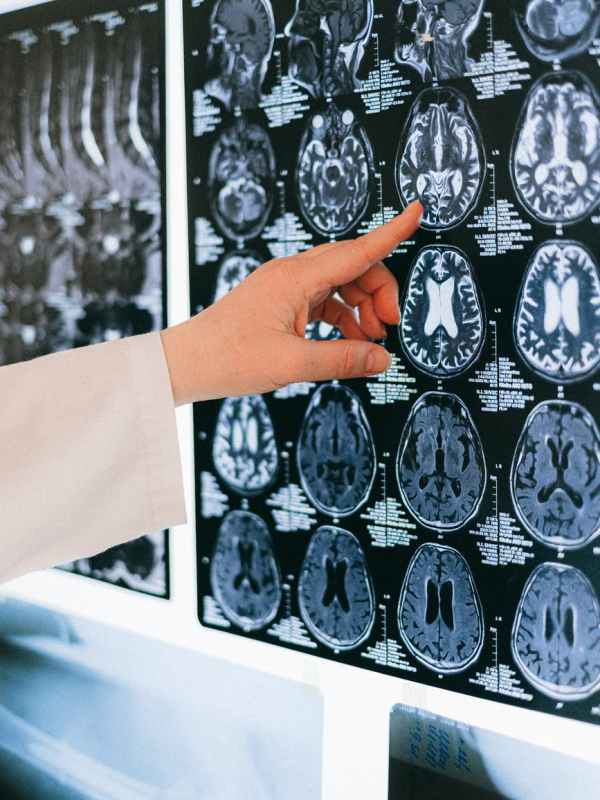

Why Antidepressants Take So Long to Work

WIRED A clinical trial reveals the first evidence of how the brain restructures physically in the first month on SSRIs—and the link between neuroplasticity and depression. CLINICAL DEPRESSION IS considered one of the most treatable mood disorders, but neither the condition nor the drugs used against it are fully understood. First-line SSRI treatments (selective serotonin…